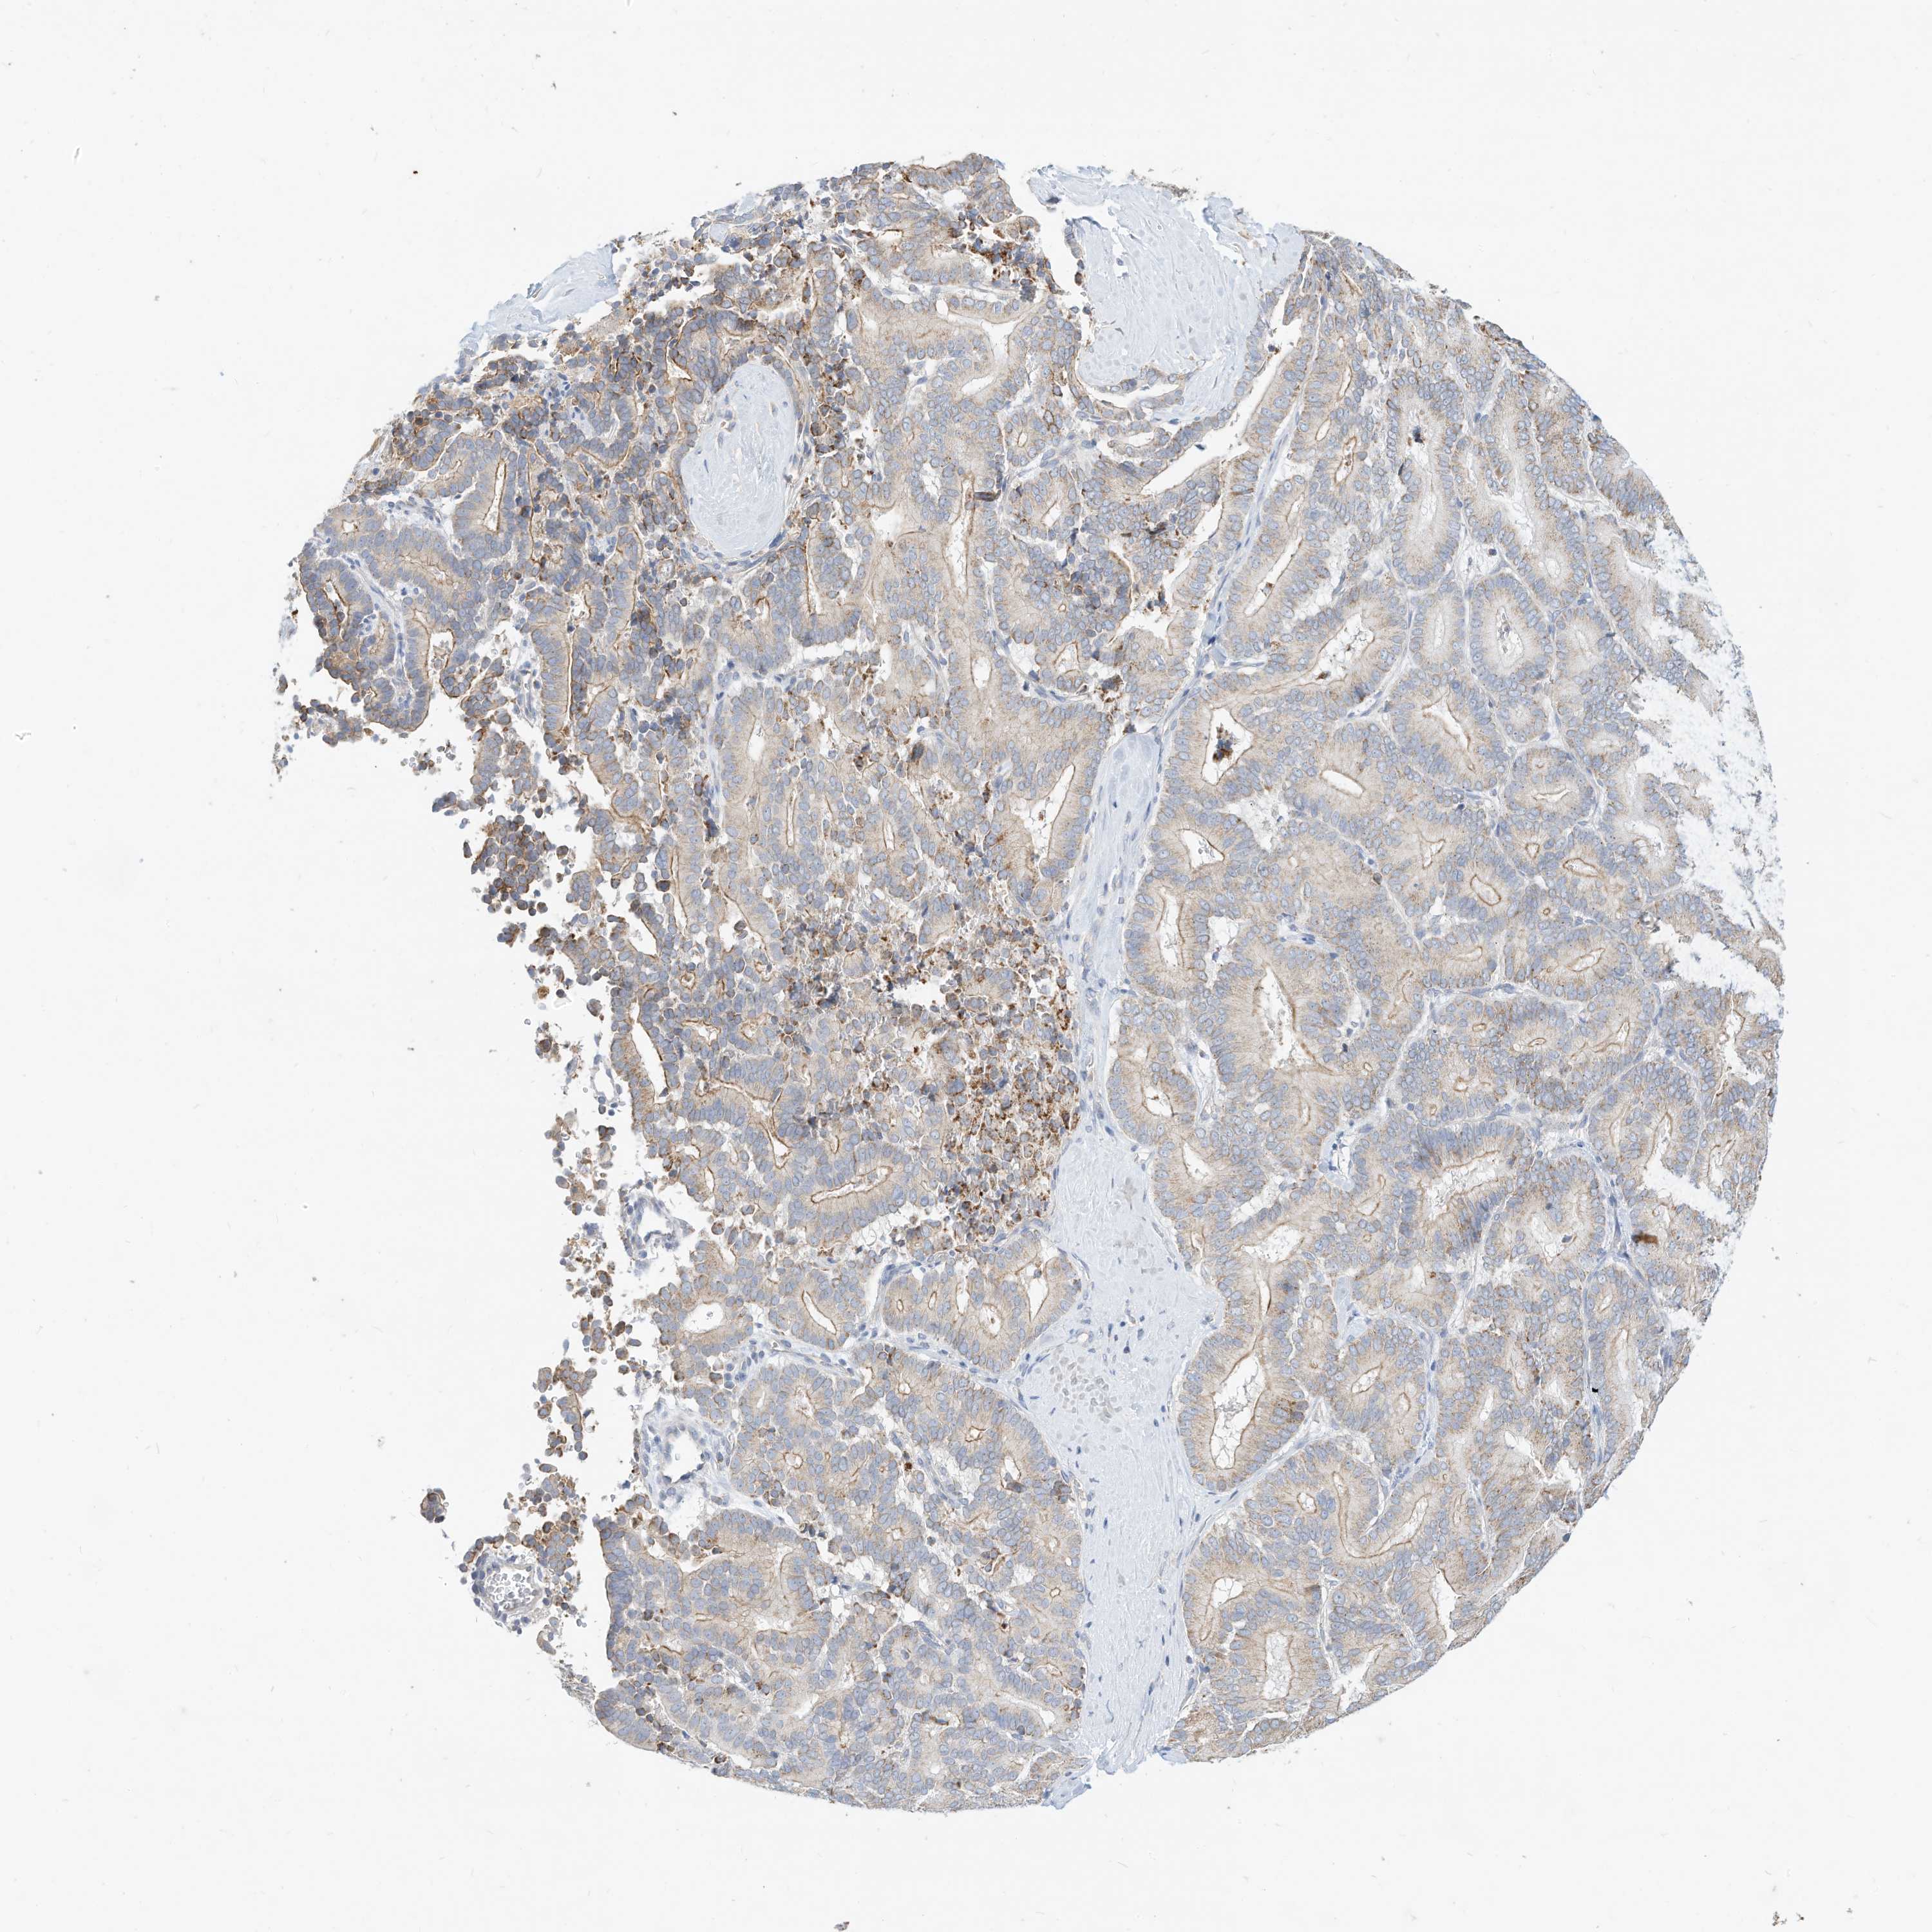

LIVER CANCER - Protein expressioni

A mouse-over function shows sample information and annotation data. Click on an image to view it in a full screen mode. Samples can be filtered based on level of antibody staining by selecting one or several of the following categories: high, medium, low and not detected. The assay and annotation is described here.

Note that samples used for immunohistochemistry by the Human Protein Atlas do not correspond to samples in the TCGA dataset.

Antibody stainingi

Antibody staining in the annotated cell types in the current human tissue is reported as not detected, low, medium, or high, based on conventional immunohistochemistry profiling in selected tissues. This score is based on the combination of the staining intensity and fraction of stained cells.

Each image is clickable and will lead to virtual microscopy that enables deeper exploration of all samples and also displays staining intensity scores, fraction scores and subcellular localization as well as patient and tissue information for each sample.

Antibody HPA030345

Staining

High

Medium

Low

Not detected

Intensity

Strong

Moderate

Weak

Negative

Quantity

>75%

75%-25%

<25%

None

Location

Nuclear

Cytoplasmic/membranous

Cytoplasmic/membranous,nuclear

Cholangiocarcinoma